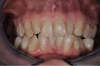

AVANT

Réalisation d'un traitement d'orthodontie par des aligneurs invisibles, des gouttières transparentes, qui ont permis un réalignement des dents de manière discrète.